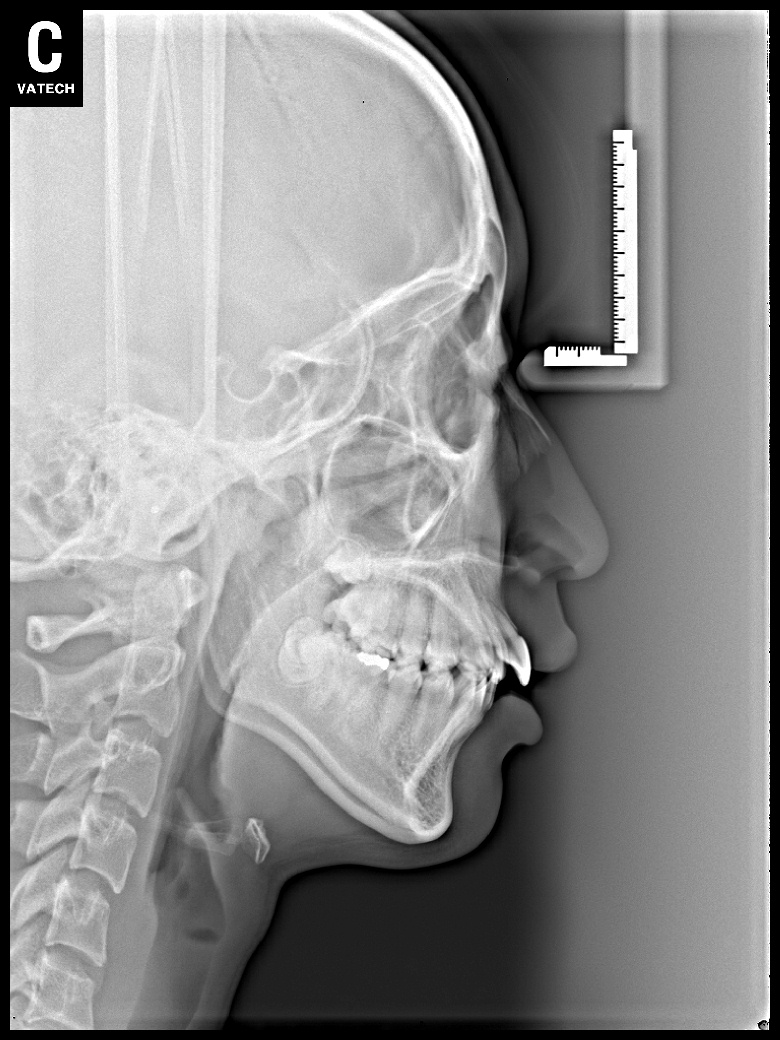

치료 전 사진입니다.